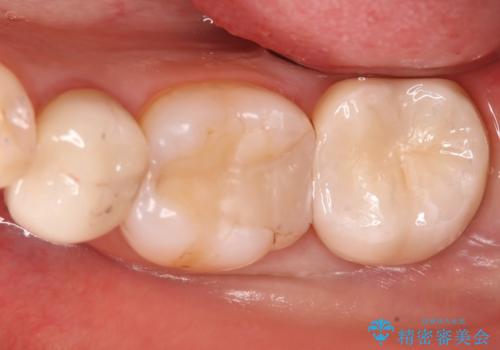

- 奥歯に虫歯があると言われて治療された患者様です。

何度か同じ歯に保険治療で治したそうですが、欠けたり再度う蝕になってしまった経験から自費治療を希望され、丈夫でキレイなセラミッククラウンにて治療いたしました。

噛み合わせや食べ物の詰まりなどは問題なく、経過良好とのことで満足いただけました。